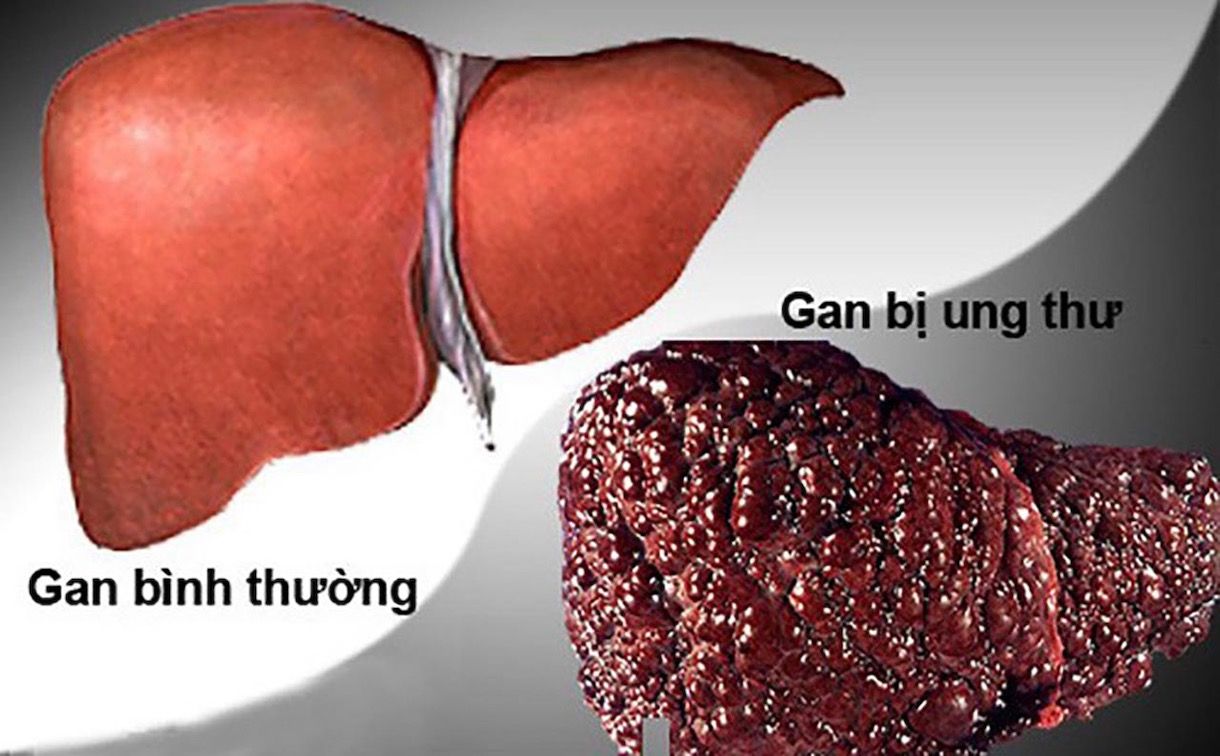

Bệnh gan nhiễm mỡ có thể làm tăng nguy cơ ung thư gan hoặc các loại ung thư khác, bao gồm ung thư đại trực tràng. Nhiều người mắc gan nhiễm mỡ cũng có các yếu tố nguy cơ ung thư khác, chẳng hạn như béo phì.

Gan nhiễm mỡ có liên quan đến nguy cơ cao hơn mắc ung thư gan và một số loại ung thư khác, bao gồm ung thư đại trực tràng. Mối liên hệ này có thể một phần do những thay đổi trong gan và một phần do các yếu tố nguy cơ chung.

Sẹo gan, còn gọi là xơ gan, là yếu tố nguy cơ hàng đầu dẫn đến ung thư biểu mô tế bào gan. Tình trạng viêm gan mạn tính có thể là nguyên nhân chính khiến xơ gan làm tăng nguy cơ ung thư gan.

Trong một nghiên cứu lớn tại Thụy Điển năm 2022, các nhà nghiên cứu phát hiện nguy cơ ung thư biểu mô tế bào gan ở người bị NAFLD cao hơn 12,18 lần so với dân số chung. Ngoài ra, những người này cũng có nguy cơ mắc bất kỳ loại ung thư nào cao hơn 1,22 lần.

Trong một số trường hợp, mỡ tích tụ trong gan có thể giống ung thư gan trên hình ảnh.

Gan nhiễm mỡ có thể trông giống ung thư trên CT hoặc siêu âm không?

Một nghiên cứu ca bệnh năm 2023 báo cáo một trường hợp mà tổn thương mỡ trong gan không thể phân biệt với ung thư gan bằng siêu âm, CT và MRI. Cần sinh thiết để xác định chẩn đoán.

Nhân viên y tế không phải lúc nào cũng phân biệt được ung thư gan và gan nhiễm mỡ trên các xét nghiệm hình ảnh. Trong những trường hợp này, có thể cần sinh thiết và xét nghiệm máu.